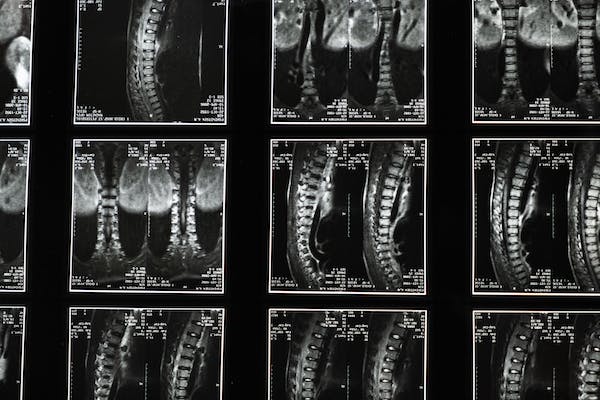

- An MRI scan, which produces clearer images of the soft tissues of the neck;

- A CT scan, which allows your doctor to see your spinal canal and any bone spurs; an electromyography (EMG), which analyses the electrical impulses of the muscles at rest and during contractions;